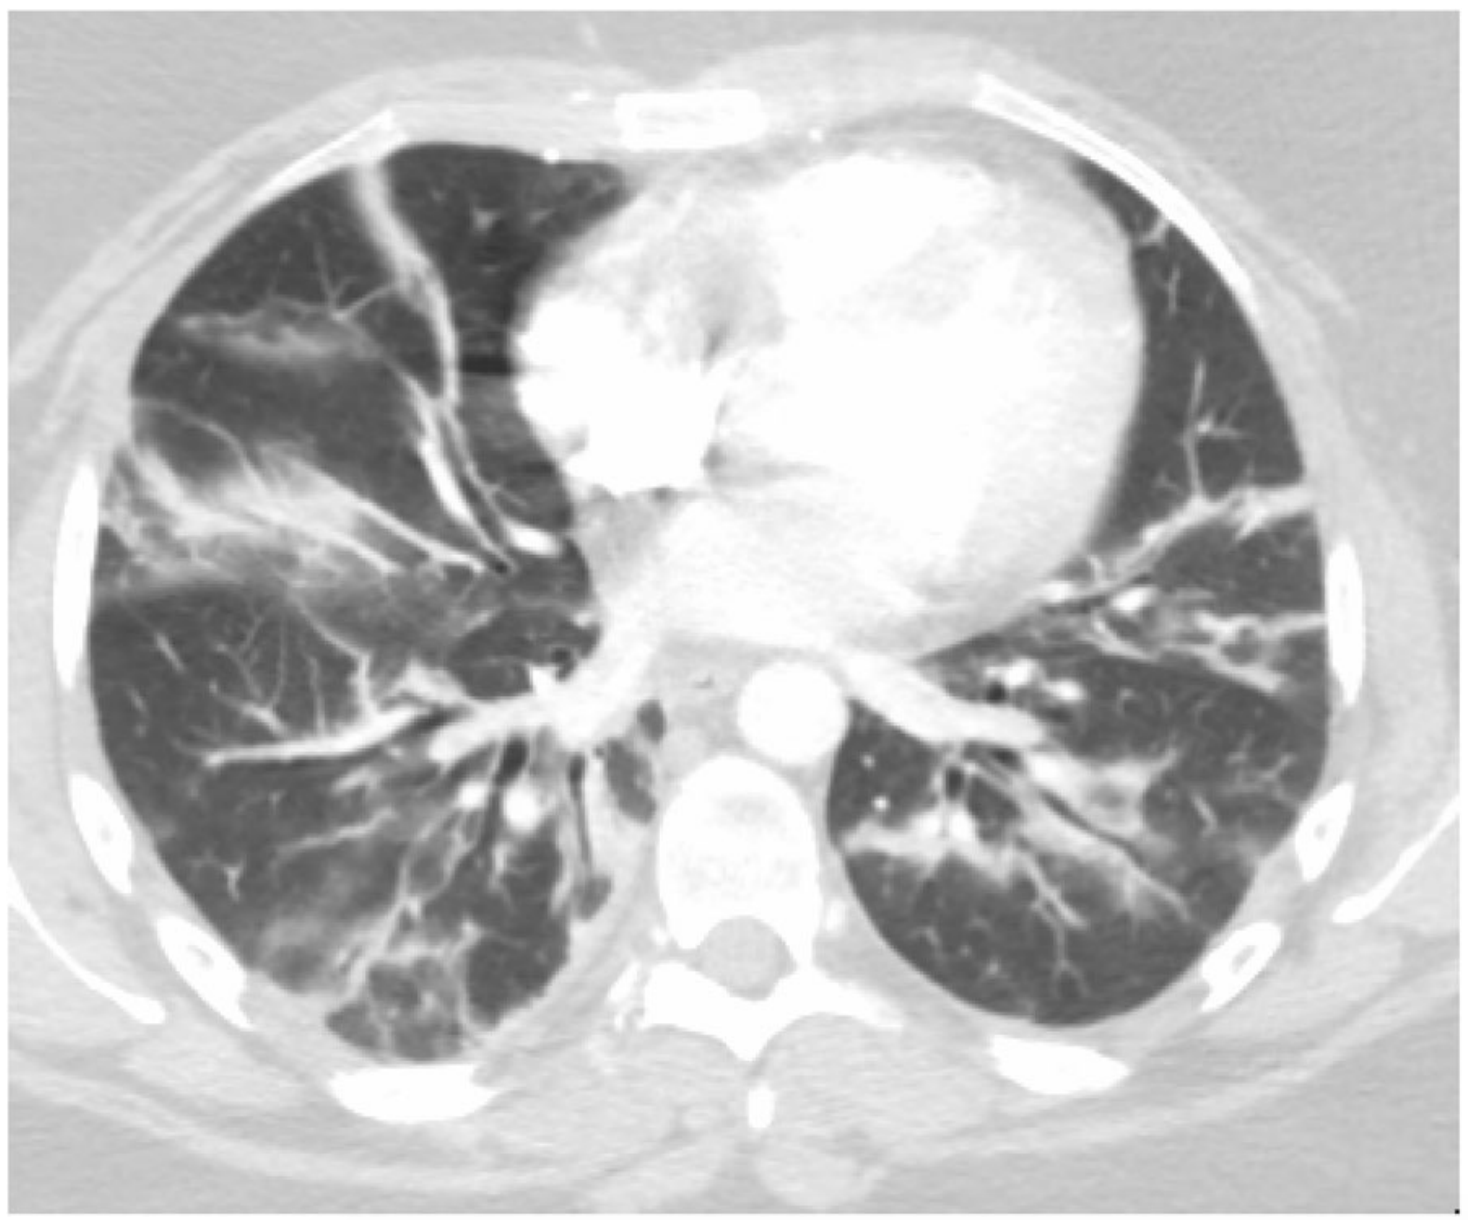

Участки по типу консолидации